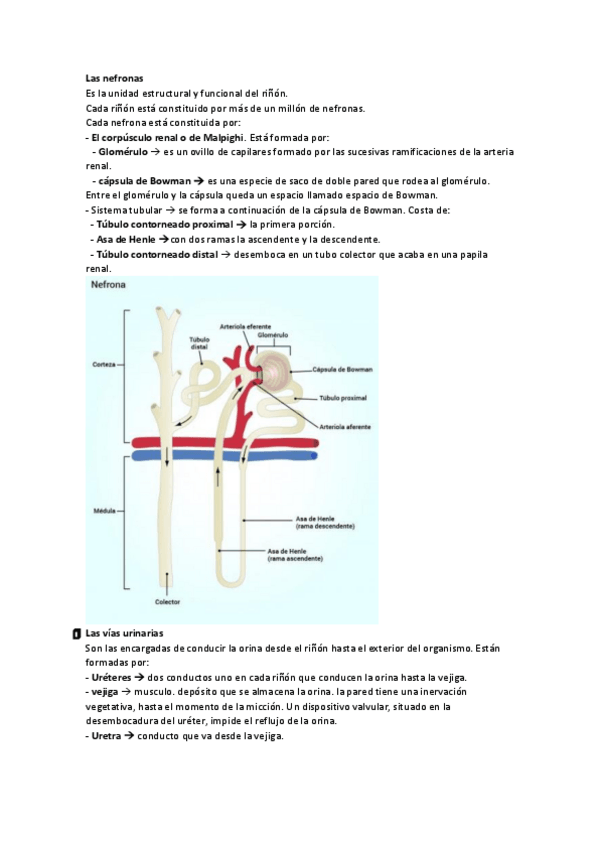

He publicado nuevos apuntes de Fisiopatología general: EL-aparato-urinario.pdf